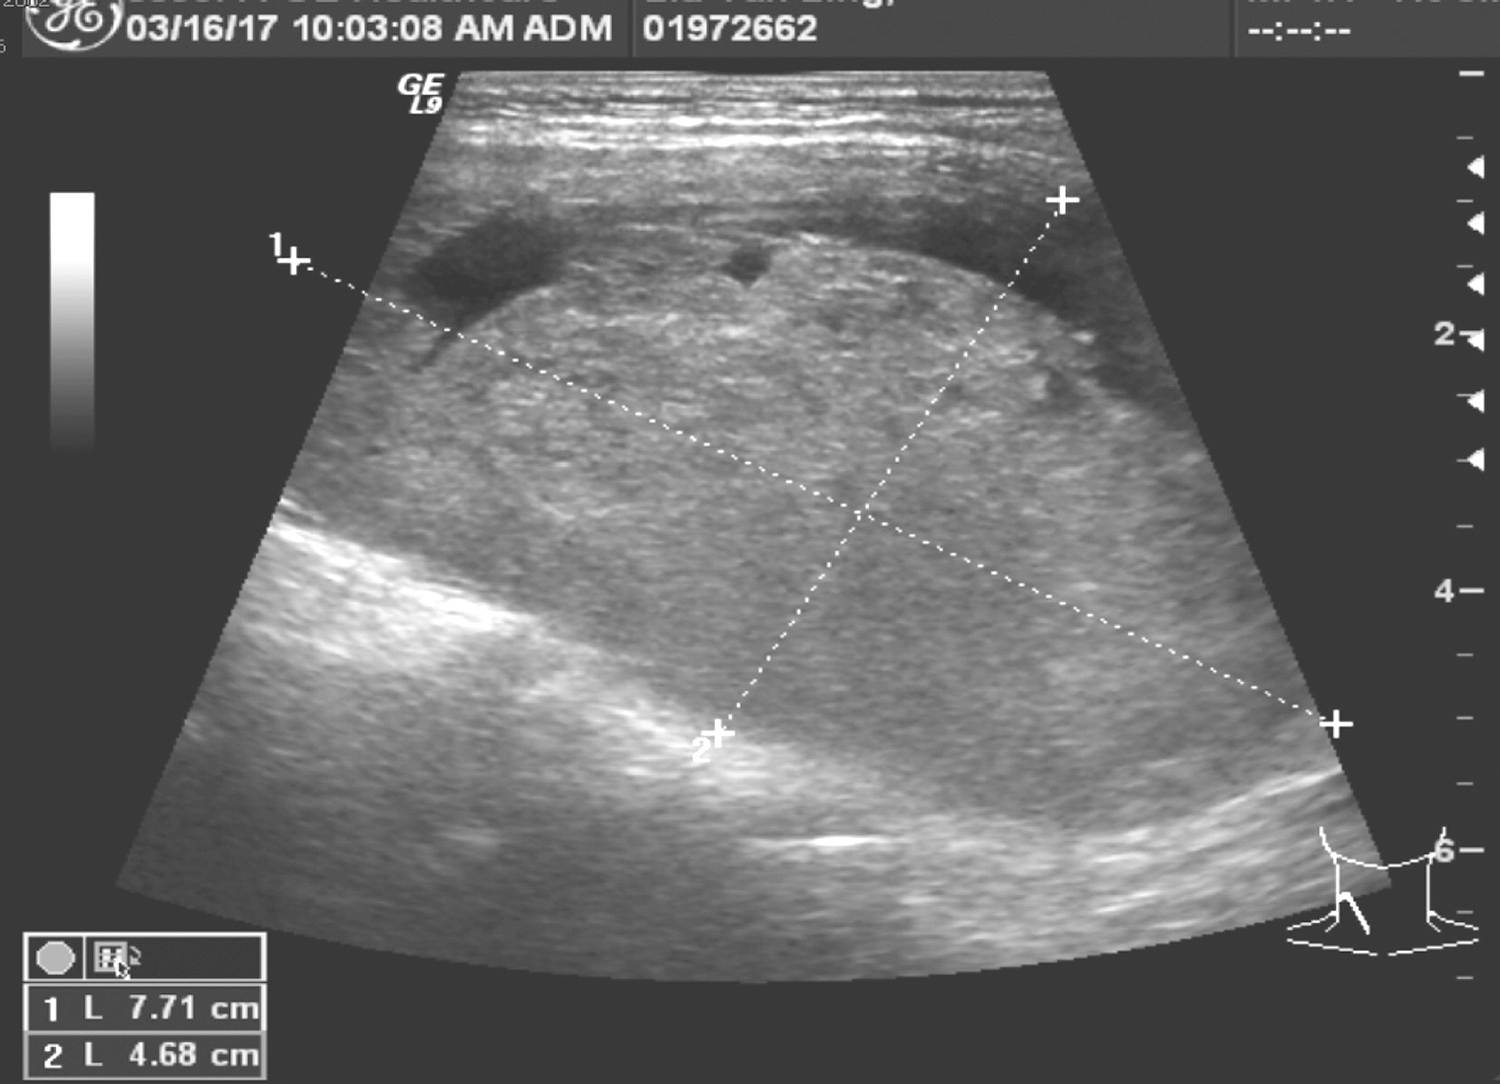

胸内甲状腺肿合并甲状腺乳头状癌一例

1小时条评论51岁男性因体检发现甲状腺肿物3周入院。如何诊治?是否需要手术? 【病例简介】 患者男性,51岁。因体检发现甲状腺肿物3周于2017年3月23日收住院。3周前患者家属发现患者颈部肿胀,无声音嘶哑,无吞咽和呼吸困难。在当地医院检查,颈部超声示:甲状腺右叶囊...